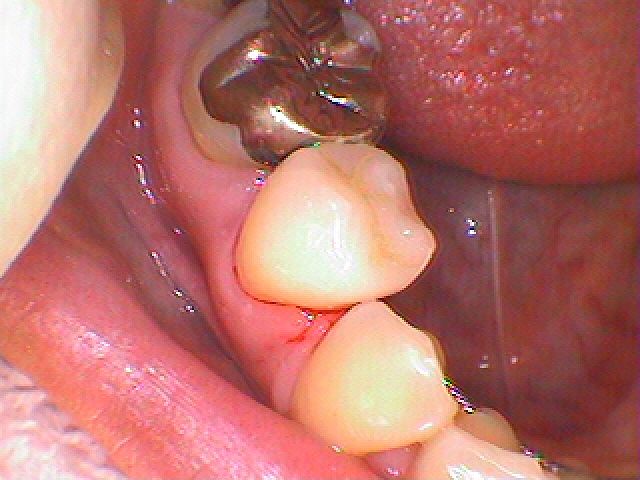

問題の歯になります

この銀歯を外していきます